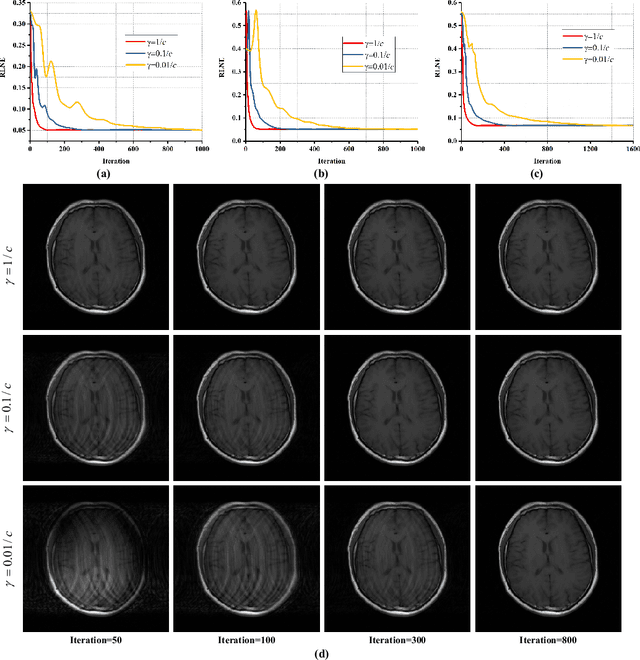

The boom of non-uniform sampling and compressed sensing techniques dramatically alleviates the prolonged data acquisition problem of magnetic resonance imaging. Sparse reconstruction, thanks to its fast computation and promising performance, has attracted researchers to put numerous efforts on it and has been adopted in commercial scanners. Algorithms for solving the sparse reconstruction models play an essential role in sparse reconstruction. Being a simple and efficient algorithm for sparse reconstruction, pFISTA has been successfully extended to parallel imaging, however, its convergence criterion is still an open question, confusing users on the setting of the parameter which assures the convergence of the algorithm. In this work, we prove the convergence of the parallel imaging version pFISTA. Specifically, the convergences of two well-known parallel imaging reconstruction models, SENSE and SPIRiT, solved by pFISTA are proved. Experiments on brain images demonstrate the validity of the convergence criterion. The convergence criterion proofed in this work can help users quickly obtain the satisfy parameter that admits faithful results and fast convergence speeds.